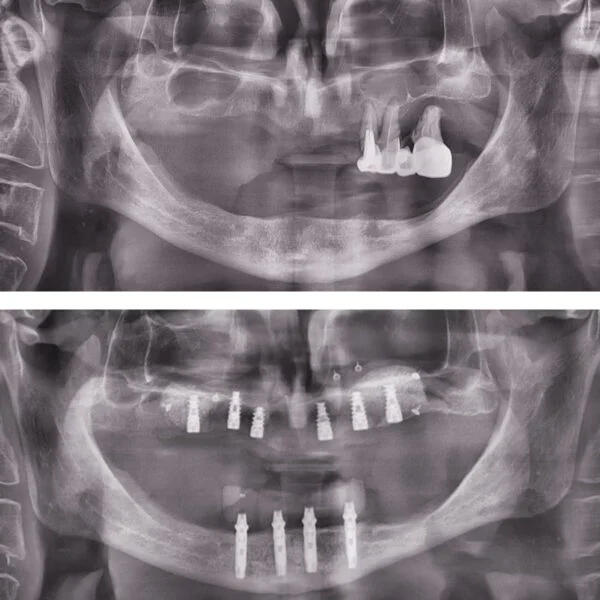

Implantul dentar este adesea recomandat deoarece prezintă foarte multe avantaje, iar, de multe ori, este unica soluție pentru protezarea unei edentații.